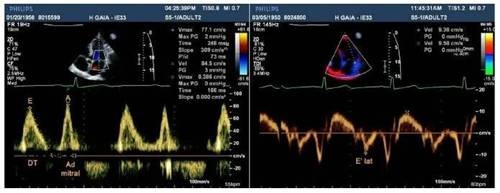

2.1.1. Cách xác định tỷ số S/D: Tín hiệu Doppler của dòng chảy qua van ba lá (tâm thu và tâm trương) được thực hiện tại mặt cắt bốn buồng tim từ mỏm. Thời khoảng tâm thu được xác định là thời gian toàn bộ của dòng hở van ba lá. Thời khoảng này bao gồm cả thời gian co đồng thể tích và giãn đồng thể tích trên hình ảnh Doppler. Thời khoảng tâm trương là thời gian còn lại của chu chuyển tim, đó là khoảng thời gian giữa hai phổ Doppler của dòng hở van ba lá hay là khoảng thời gian đổ đầy thất phải.

Tần số tim được xác định dựa trên hình ảnh điện tâm đồ kèm theo trên màn hình siêu âm và các thông số của dòng chảy qua van ba lá (tâm thu và tâm trương) được lấy là giá trị trung bình của ba chu chuyển tim (hình minh họa).

Hình minh hoạ cách xác định tỷ số S/D từ phổ Doppler của dòng chảy qua van ba lá